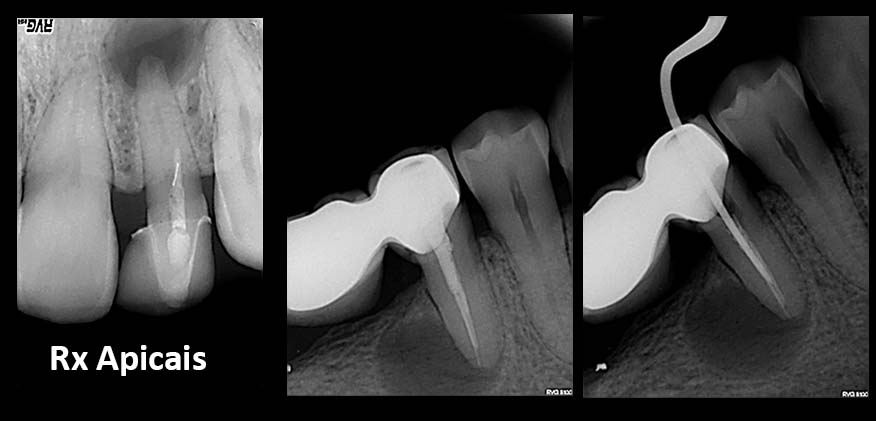

• Radiographies/X´Rays

• If necessary additional exames are taken (TAC)